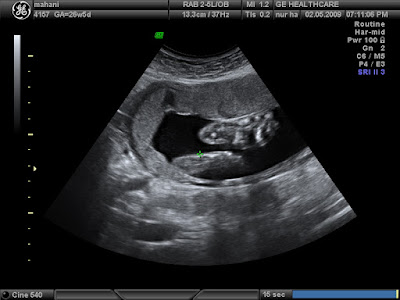

12.8.09

Satu Dua Sifar Lapan

Ahtok Jr.

Tarikh lahir :

12 Ogos 2009 @ 12.03pm

Tempat lahir :

Titik tengah Semenanjung Malaysia

Kelahiran :

Normal

Berat :

3Kg 200g

Agama :

Islam

Bangsa :

Melayu Malaya

Darah :

Kacukan

Misi :

Amal ma'ruf, nahi mungkar

Motto :

Berkata jujur sekalipun pahit

Cita-cita :

Menjadi anak yang soleh

Kelebihan :

Minda dan mata yang tajam

Suapan pertama :

Madu dan kurma

Kalimah pertama didengar :

Azan & iqamah

Makanan kegemaran :

Susu ibu lemak berkrim

Makanan lain :

Makanan santapan akal, rohani & jasmani

Alahan :

Tiada

Titipan doa bapa :

"Aku berlindung dengan kalimat Allah yang amat sempurna dari segala gangguan syaitan dan juga dari segala haiwan yang berbisa dan juga dari pandangan mata yang jahat"

(HR Ibnu Sunni)

Awek gua kena kuarantin di wad. Bukan dia saja-saja nak masuk wad tu. Dia pun tak hingin tidur situ. Tapi itulah yang berlaku setelah dia melepasi jangkaan hari bersalin selama seminggu. Jadi, sementelahan dia masuk wad sehari semalam. Entah mungkin jejak dua malam. Gua lah yang menjaga puteri-puteri kecil yang ditinggalkan. Bukan gua nak menunjuk-nunjuk bahawa gua ni bagus sangat. Itulah kebiasaan yang gua lakukan. Tapi, zaman sekarang mana ada lu jumpa bapa sehebat gua. Muda dan kacak juga pulak tu. Adoyai... Jaga kebajikan puteri kecil dengan penuh komitmen. Bagi makan, mandi, minum susu. Tukar pakai. Bagi tidur. Bagi hiburan. Yang penting bagi kasih sayang yang tidak berbelah bahagi. Kasih sayang tak ada dijual di kedai-kedai beb!

Tapi gua akui, gua buat sehabis baik mana sekalipun, awek gua buat lagi sepuluh kali ganda lebih baik . Awek gua memang best of the best. Semoga awek gua selamat melahirkan untuk kali yang ketiga. Dan agar semuanya berjalan lancar. Sesungguhnya awek gua lah orang yang paling tabah di kaca mata gua. Harap-harap dia tak baca entri ni. Bukan apa, takut prestasi merundum dengan pujian.